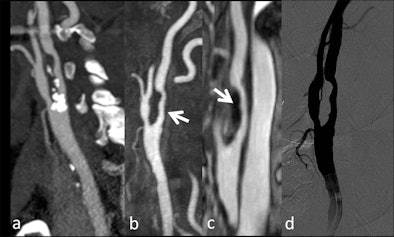

| Patient with transient ischemic attack. A: CT angiography depicted a large plaque with a calcified component involving the internal carotid artery; first-pass (B) and high spatial resolution images acquired during the equilibrium phase of an intravascular contrast agent (C) allowed the visualization of the surface irregularities of the soft component of the plaque (arrows). These findings were confirmed by conventional angiographic study (D). (Provided by Prof. Carlo Catalano and Dr. Beatrice Cavallo Marincola) |